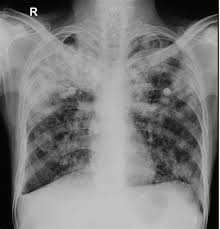

Black Spot On Kidney X Ray. X ray abdomen is simple cost effective and better choice to diagnose. A spot is not a standard descriptor it doesn t really mean anything from a radiology standpoint.

By cathey newton134465 4 posts last post over a year ago. Yesterday was my xray day because im having this back pain so they check if somethings wrong with my kidney. So im kind of worried still about that.

My doctor told me that my kidneys were ok but he was wondering about that black stuff. What might it be. By cathey newton134465 4 posts last post over a year ago. Rapid muscle tone loss.